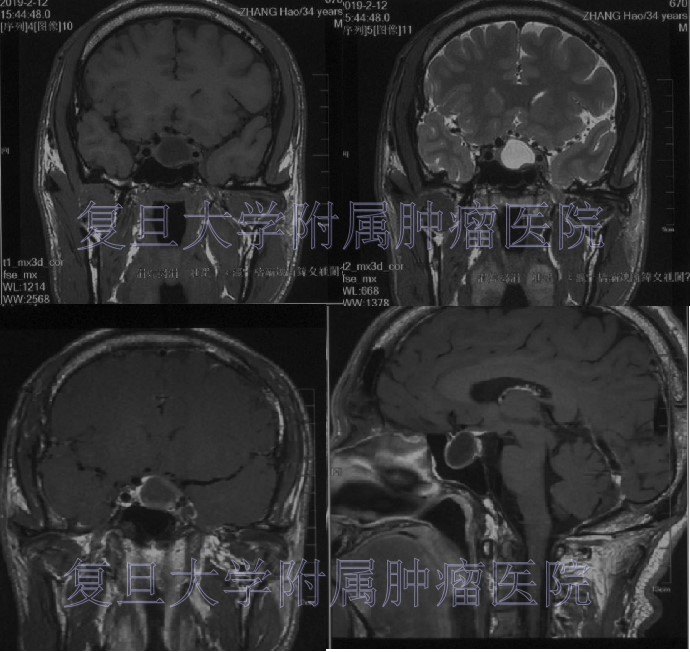

进一步查磁共振检查示:鞍区囊性占位性病变,T1低信号,T2高信号,增强后周边环形强化。遂就诊于我院神经外科。

根据患者临床表现、影像学及激素检查,初步诊断为:肢端肥大症,GH型垂体瘤